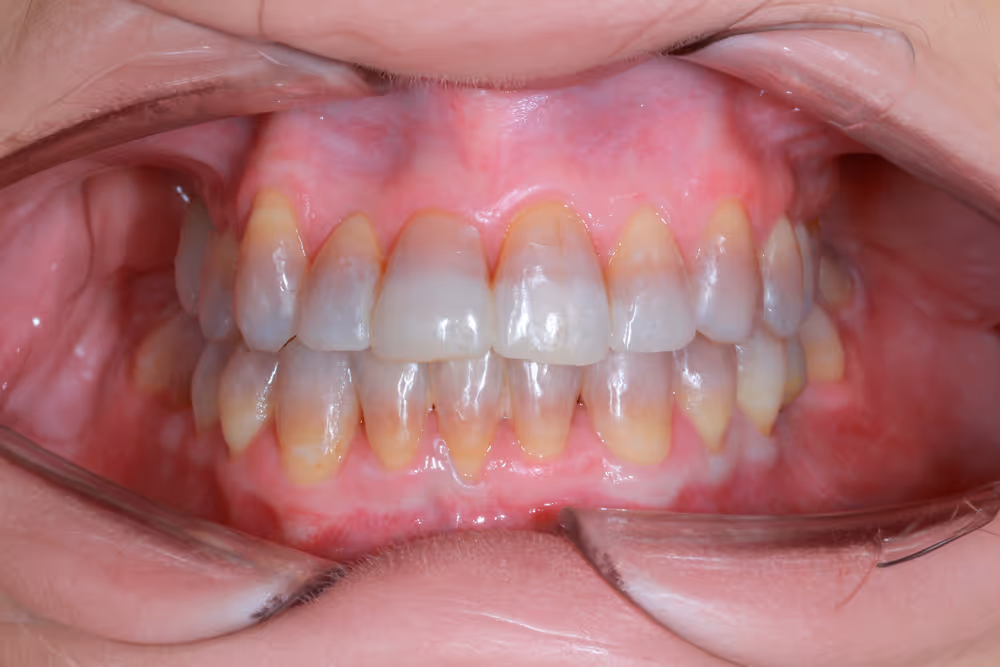

Te invitamos a conocer algunos de nuestros casos clínicos, donde podrás comprobar de primera mano la transformación que podemos lograr gracias a un enfoque multidisciplinar y a la excelencia que aplicamos en cada paciente.

En cada uno de estos casos, la especialización en las diferentes áreas de la odontología, el trabajo en equipo y la atención individualizada han sido claves para conseguir resultados óptimos.